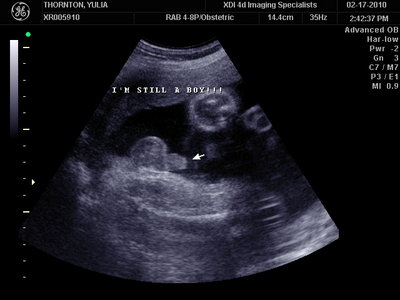

А это в 30 недель

| Вложения: |

MY BABY SONO!_20.JPG [ 94.63 КБ | Просмотров: 1239 ]

Sweetheart75 писал(а): Ну ладно, тогда и я нашего писюна покажу  Надеюсь, Джеффри на меня не обидится Вот это в 23 недели: (там оборудование переключалось из режима 3Д в обычный 2Д) Oоо, такое достоинство невозможно не заметить  А в 30 недель так вообще!